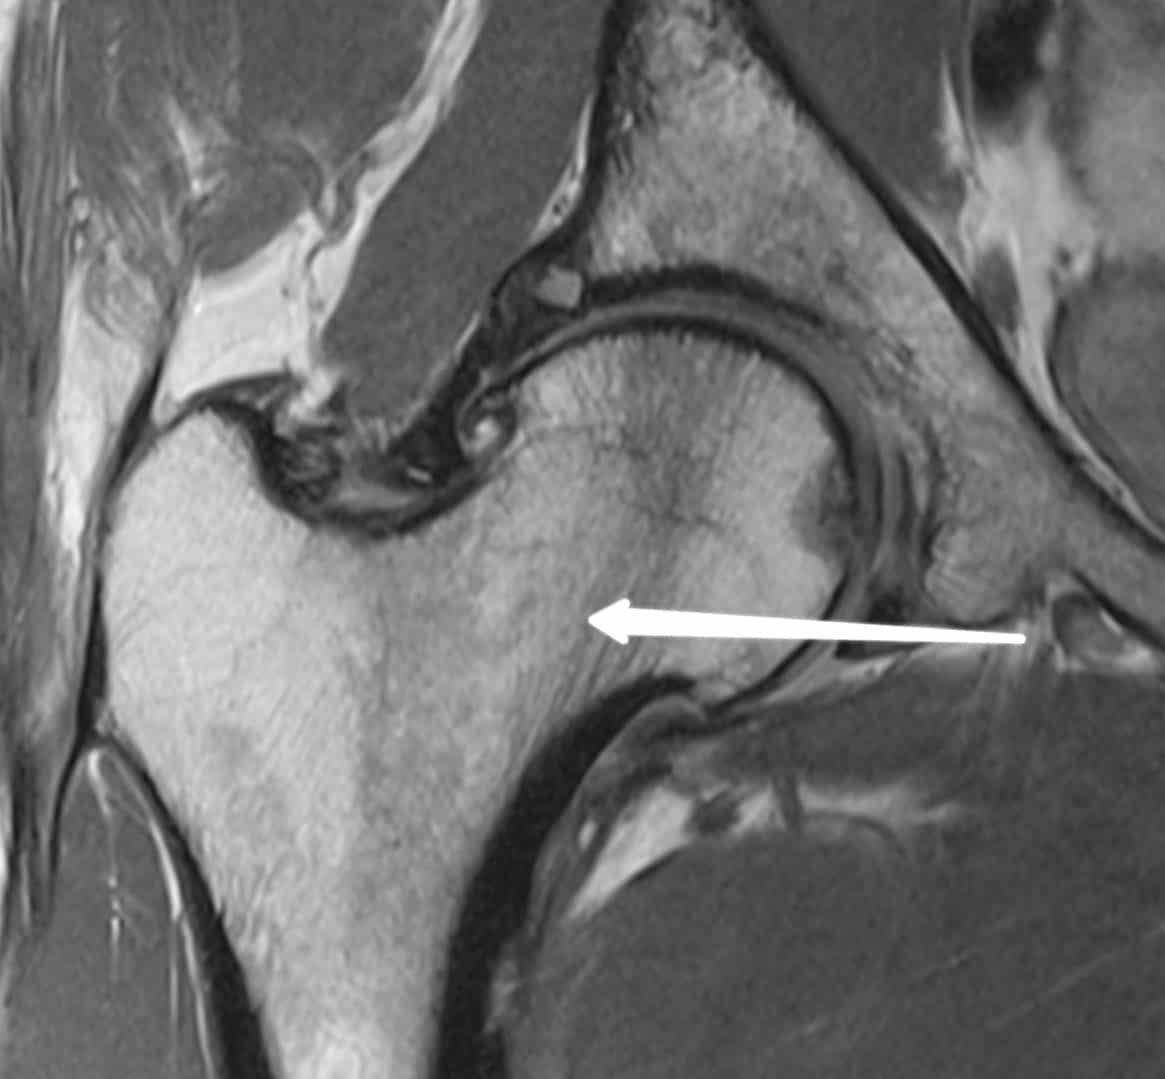

Sample cases for the FRCR 2B

Check a few sample FRCR 2B viva cases courtesy Revise Radiology telegram group:

Long cases: